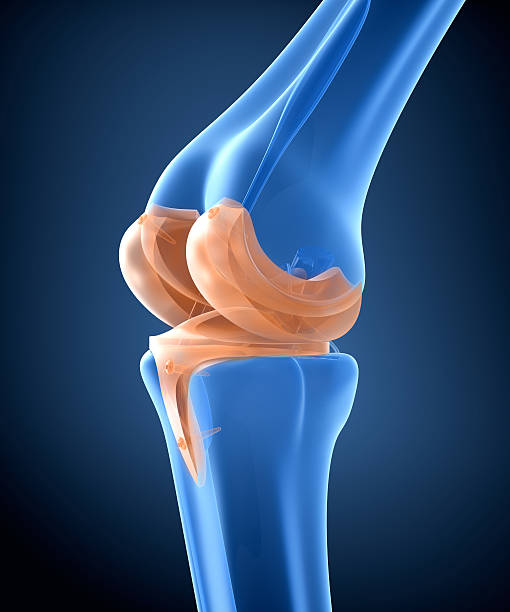

슬개골염에 의한 무릎 통증

슬개골염은 슬개골 연골과 연결된 퇴행성 질환으로, 무릎 관절 내부에서 연골의 변성이 진행됨에 따라 발생합니다. 무릎 통증, 관절 강직, 충수성 부종 등의 증상을 일으키며, 보행이나 운동 시 통증이 더욱 심해질 수 있습니다. 치료는 운동 치료, 약물 치료, 수술적 치료 등이 있으며, 초기 단계에서 조기에 진단하고 치료를 시작하는 것이 중요합니다.